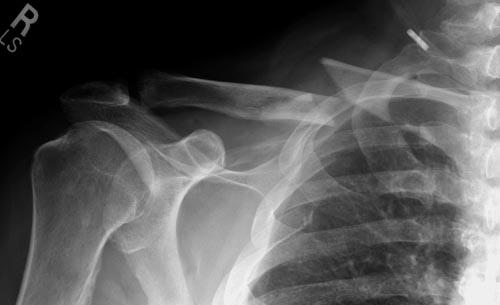

Уважаемые коллеги. Обратился пациент 29лет, оперирован в 2007 г. в Республиканском центре по поводу перелома ключицы и/м спицей, после несращения повторно оперирован в 2008 году, со слов больного освежение и повторно фиксация спицами, и обратился только через 6 лет, активные и пассивные движения в правом плечевом суставе в полном объеме, беспокоит только слабость при поднятии тяжести и подвижность в с/з ключицы. Р-снимок прилагается.Честно признаться, пока не знаю, что делать, имеются обычные пластины из ЦИТО, спицы, может, краевая резекция до появления «росы» дефект заполнить спонгиозной костью, фиксация и/м двумя спицами, загнуть оба конца спицы с компрессей, или пластина…или вообще не трогать. Прощу не критиковать, имеем то, что имеем, пациент в НИИТО не может ехать из-за финансов. С уважением Абдурашид.